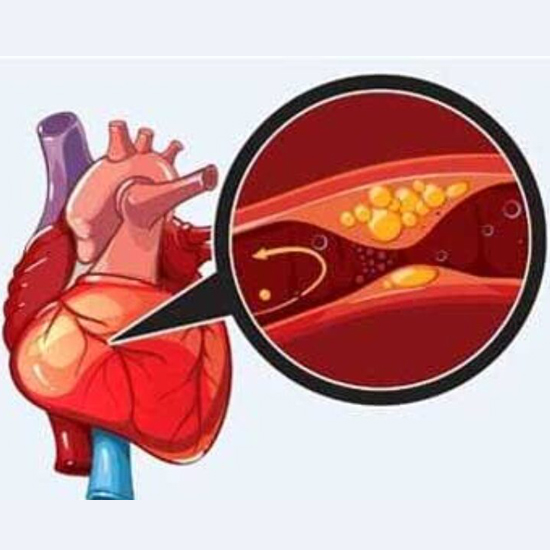

Angiography is an imaging test that uses X- rays to view your body's blood vessels.

Angioplasty also known as balloon angioplasty abd percutaneous transluminal angioplasty